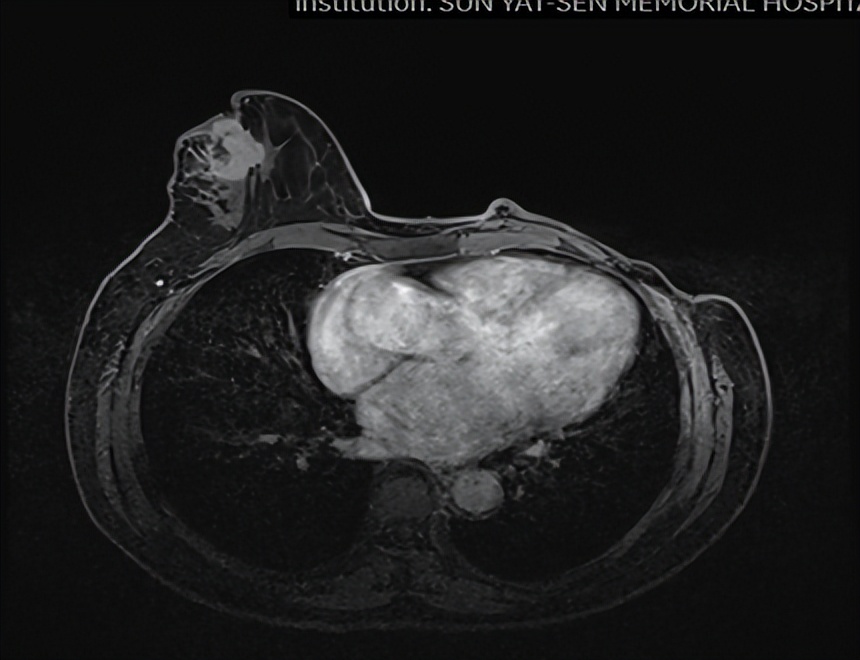

乳腺MR

右侧乳头后侧中部多个异常信号结节(较大者23*15mm),符合乳腺癌,BIRADS:5类。右侧腋下肿大淋巴结,考虑转移。

颈胸腹盆腔CT

右乳外上象限占位,考虑乳腺癌;右侧锁骨上、上纵隔及右肺门多发淋巴结转移(较大者24*15mm)。胃贲门处小弯侧胃壁明显增厚(26*12mm),考虑胃癌可能,周围脂肪间隙清;颈部未见明确异常。头颅MR未见脑转移。